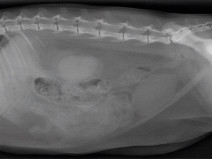

• Plan modulaire en échographie - Module avancé d'échographie abdominale

Principes du plan modulaire d’échographie :

Le plan de formation est composé d’un module de base d’échographie abdominale (2 jours), d’un module avancé en échographie abdominale pour être capable de reconnaitre les lésions abdominales les plus fréquemment rencontrées (2 jours). Pour celles et ceux qui souhaitent aller encore plus loin, nous proposons aussi 2 modules spécifiques, d’une...

Formation complète

Le plan de formation est composé d’un module de base d’échographie abdominale (2 jours), d’un module avancé en échographie abdominale pour être capable de reconnaitre les lésions abdominales les plus fréquemment rencontrées (2 jours). Pour ceux et celles qui souhaitent aller encore plus loin,...

Le plan de formation est composé d’un module de base d’échographie abdominale (2 jours), d’un module avancé en échographie abdominale pour être capable de reconnaitre les lésions abdominales les plus fréquemment rencontrées (2 jours). Pour ceux et celles qui souhaitent aller encore plus loin, nous proposons aussi 2 modules spécifiques, d’une...